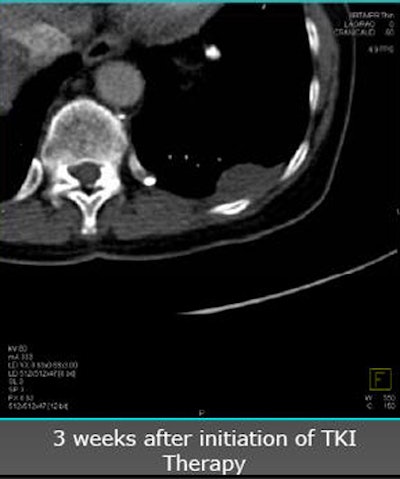

| Future studies will focus on clinical experience with angiogenic agents. In a patient with renal cell carcinoma with pleural metastasis (above), decreases in tumor perfusion are readily seen after three weeks of sorafenib antiangiogenic therapy (below). |

![]() |